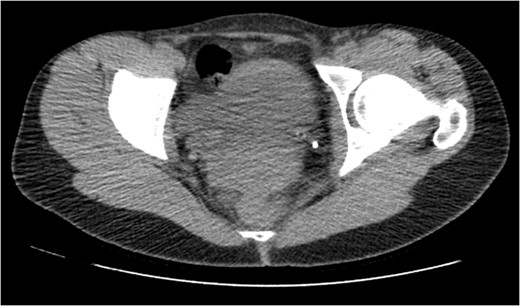

CT IVU- confirmed extravasation of contrast medium around the left kidney and ureter, the rupture being at the level of the PUJ.

Coronal view reconstructions using maximum intensity projection, showing proximal ureteric leak of contrast.